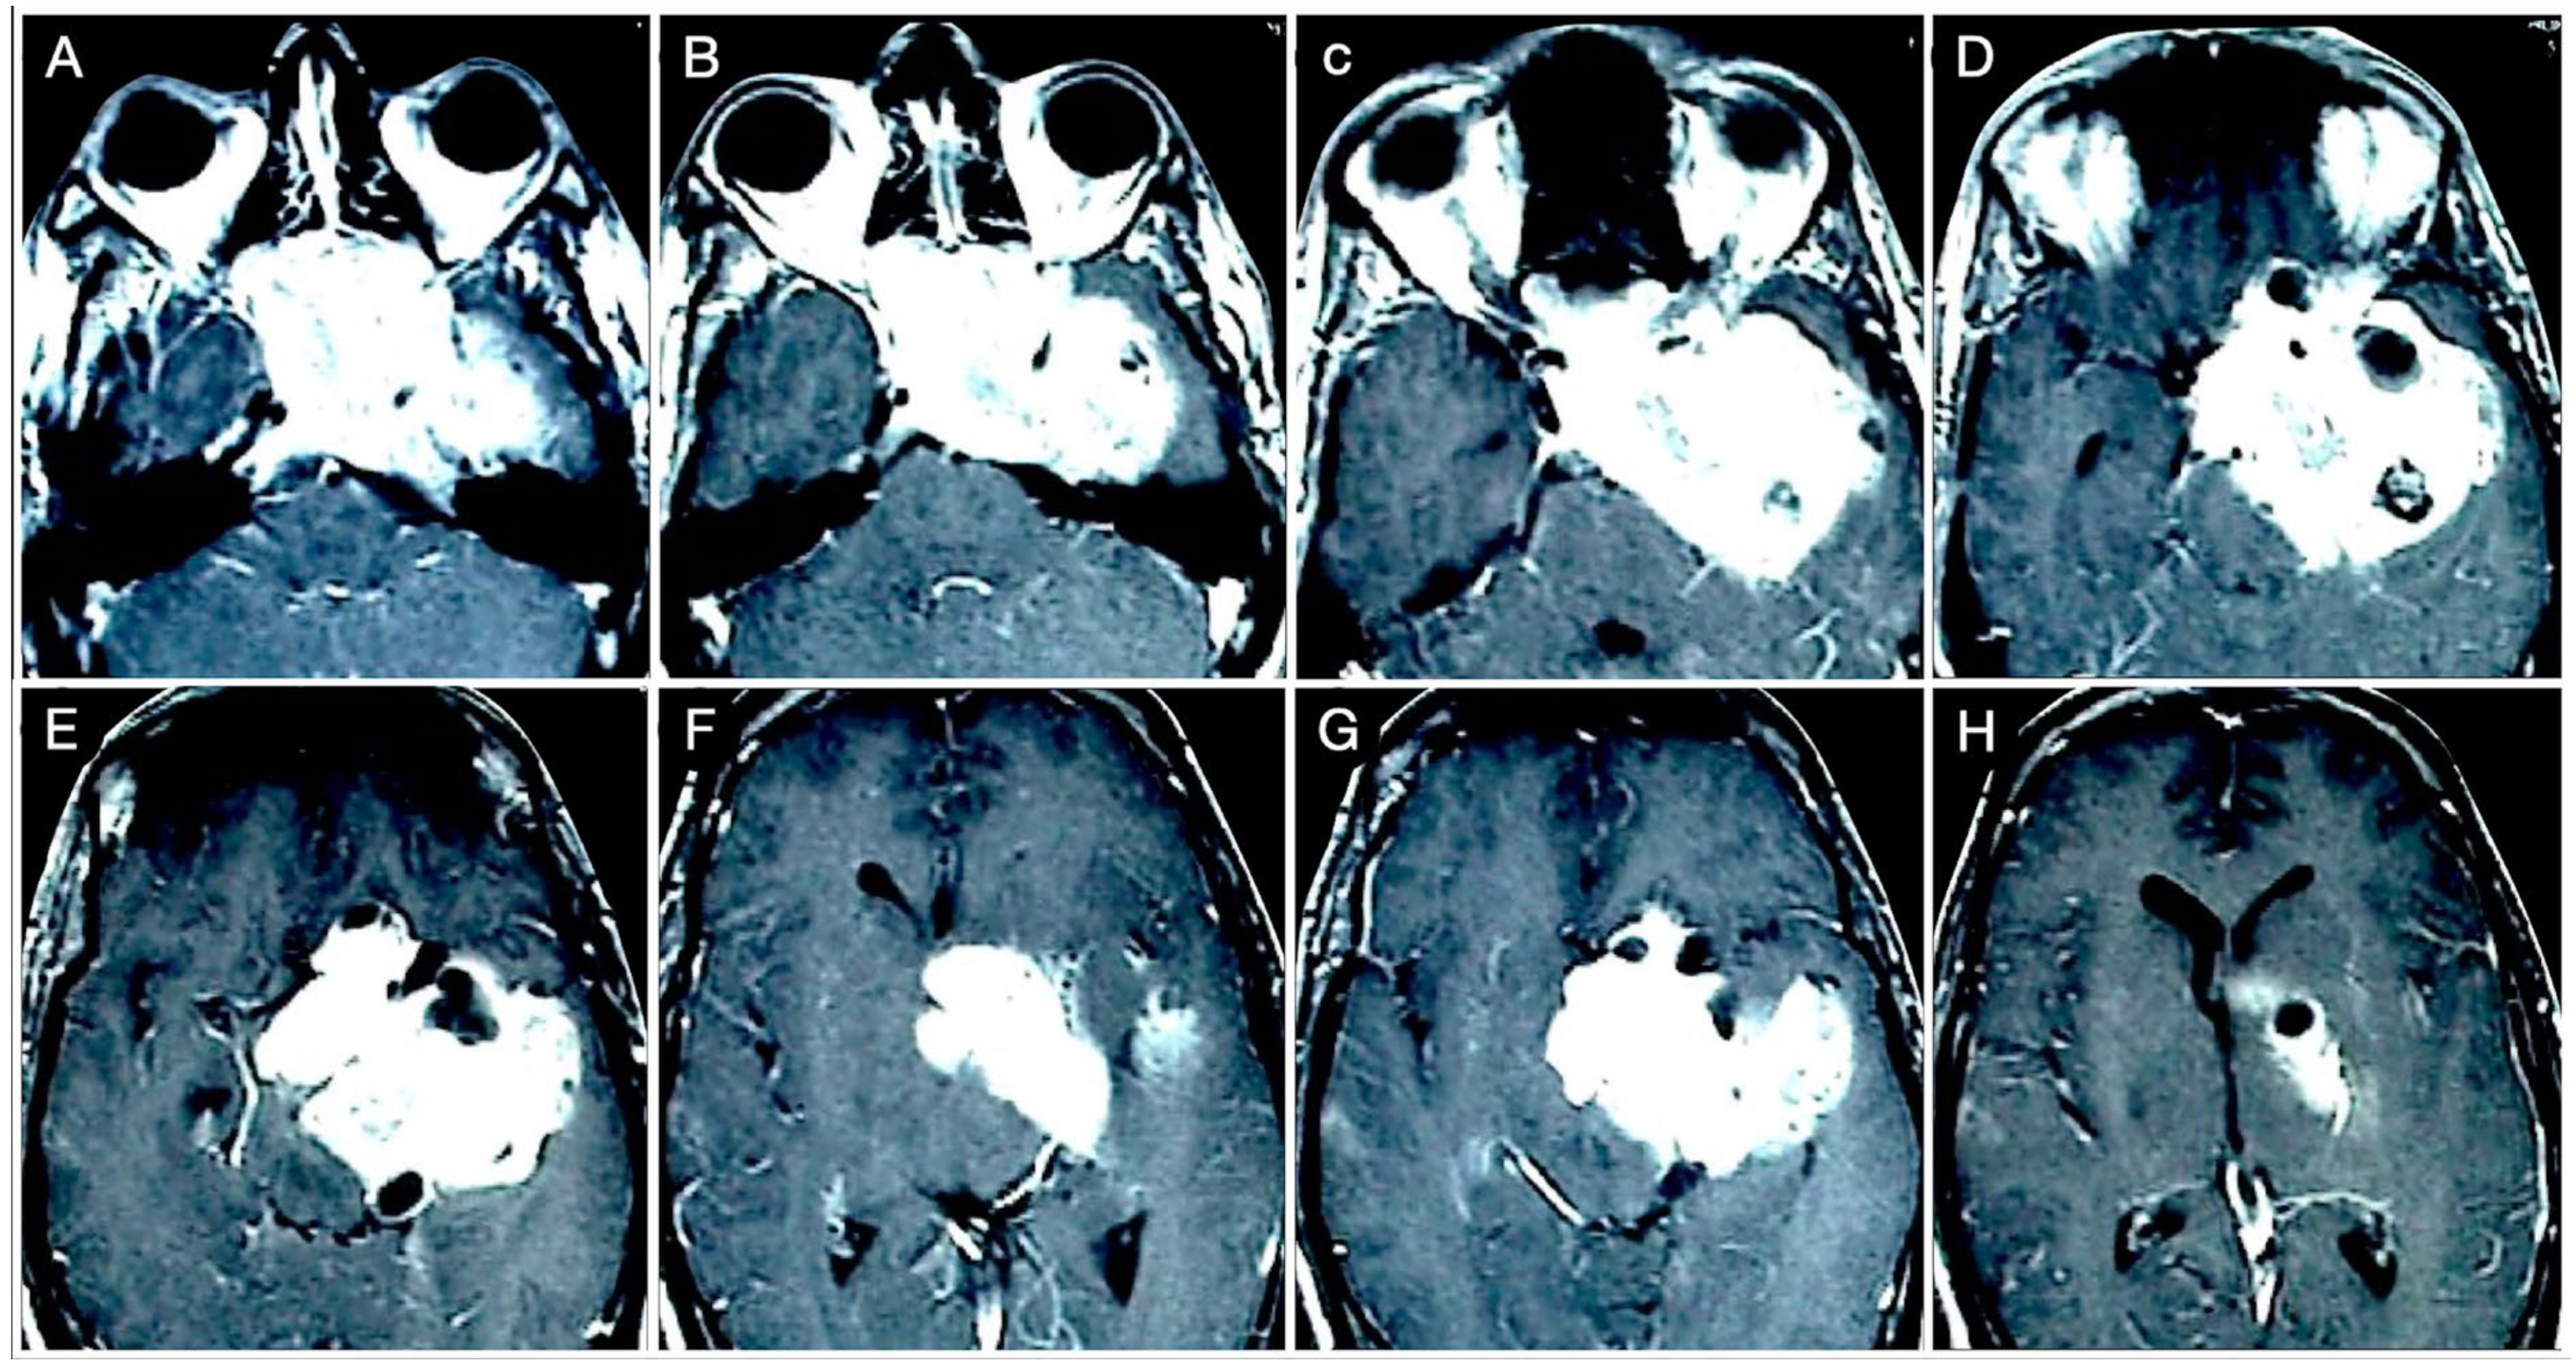

3.3.1. Case #4: Involvement of the Middle Skull Base with Parenchymal Invasion

3.3.2. Case #5: Extension beyond the Lateral Wall of the Cavernous Sinus

3.5. Arterial Encasement

3.6. Brain Parenchymal Invasion